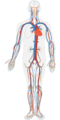

| Beschreibung | Die größte Körperschlagader ist die Aorta. |

| Originaltitel | menschlichen körper kreislauf-system

| aktuell | 12:34, 23. Nov. 2015 |  | 640 × 1.280 (458 KB) | Wweidinger (Diskussion | Beiträge) | '''Die größte Körperschlagader ist die Aorta.'''<br> Bildquelle: www.pixabay.com <br> Fotograf: CC0 ClkerFreeVectorImages |